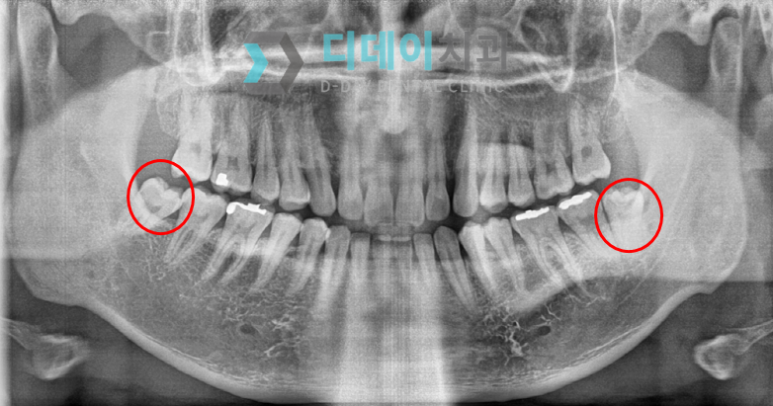

X-ray로 촬영해 보니, 사랑니가 자라난 모양은 가지런하고 좋았습니다.

잇몸에 너무 깊게 매복되어 있거나 심하게 기울여졌거나 옆 치아를 손상시키지도 않았습니다.

그러나 문제는 치아 가장 안쪽에 사랑니가 있어서 양치질이 잘 안되어 충치가 생겼다는 것입니다.

강남사랑니발치

엑스레이 사진을 자세히 보면 양쪽 사랑니 모두 충치가 심해 까맣게 보일 정도로 심각했기에 발치하기로 결정했습니다.

사랑니 2개를 동시에 발치할 경우에는 통증이 더 심할 수도 있기에 무리하지 않는 선에서 1주일 텀을 두고 발치하기로 했습니다.